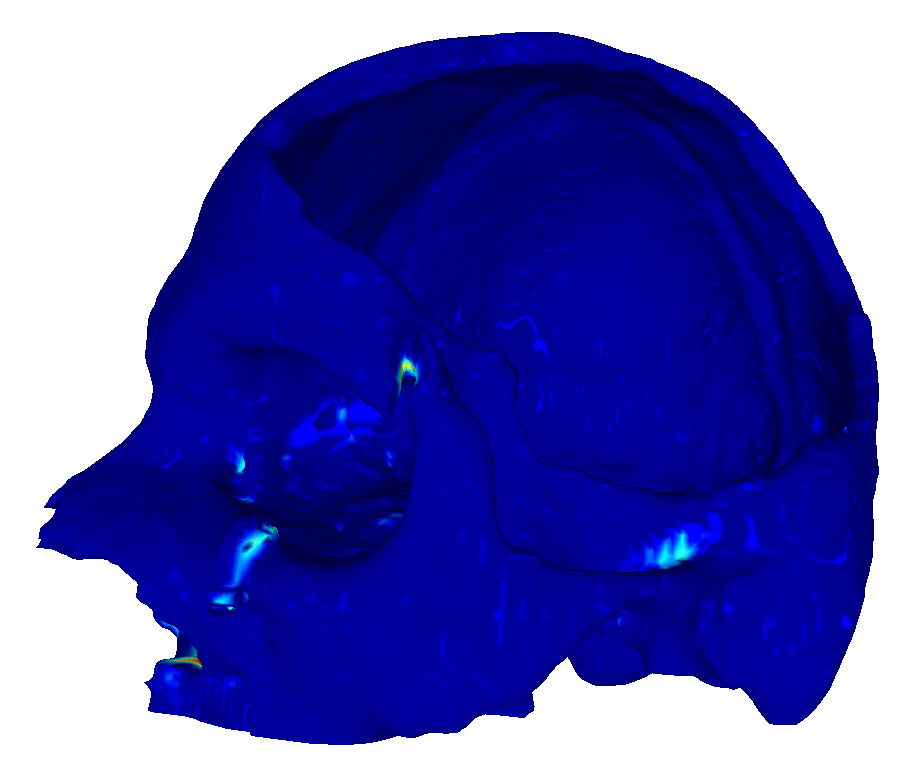

22 scans were randomly selected as test subjects for the experiment, leaving 177 skulls for model training. Using convolutional kernels of size 3 in all the CNN models results in the 3D model having the same number of trainable parameters as the sum of the three orthogonal 2D models. The comparison between the MV ensemble and the 3D approach can therefore be considered an ablation study to an extent. CutCNN models also have a similar number of parameters, the only difference being the final edge probability output layer. Quantitative comparison of results of each method are presented in Figure 4 and Table 1. Further qualitative results are shown in Figure 5 and 1.

CutCNN segmentation framework resulted in a performance gain in all cases in terms of every metric used in the experiment over standard CNN approaches. The output of CNN object probability map often contains errors near external objects or smaller tissue defects as these are scarce in the training data distribution. However, the graph-cut optimization guides the resulting binary segmentation towards a spatially consistent and compact shape, often eliminating these artifacts if a detected edge corresponds mostly to the correct object boundary. This effect is further illustrated in Fig. 1.

Our second observation is that using 3D convolutional kernels has a rather small effect on the final segmentation precision quantitatively compared to the MV approach. However, although the quantitative difference is small, for applications in medical additive manufacturing, it is important to avoid ragged segmentation output which may result from MV CNN in areas of lower model certainty. These include for example teeth, which are challenging to detect, especially when the lower and upper teeth are in contact (see Figure 5 a), or maxillary sinus, which is often enclosed in order to improve mechanical stability of the manufactured model (see Figure 5 b). Therefore, 3D U-nets are often considered necessary to avoid these discontinuities caused by slice-by-slice processing.